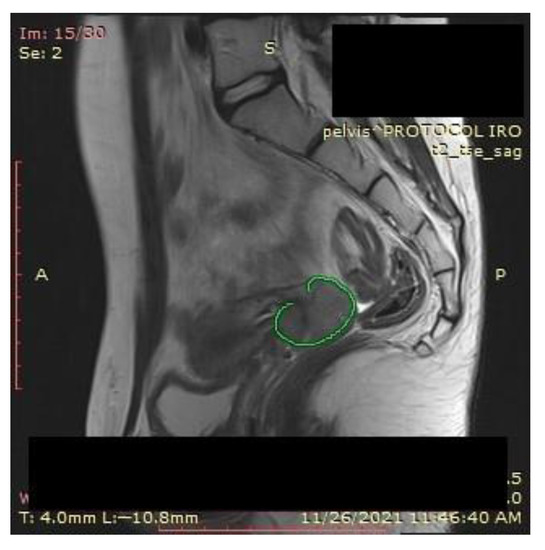

A pelvic MRI was recommended to our patient, as it would be able to provide an accurate anatomic localization of the mass and its relationship with the surrounding organs. It revealed an expansive solid cervical mass that developed between the internal and external cervical orifice, occupying the left vaginal recess, with imprecise boundaries being observed at this level. Axial and sagittal T2-weighted images showed a 53 × 78 × 46 mm mass that was hyperintense compared to normal myometrium, and axial T1-weighted images showed an isointense mass compared to the myometrium that was occupying the uterine cervix and upper vagina. The ovaries and the uterine body were normal in size, and a right external iliac adenopathy was also detected (Figure 1).

Figure 1. Pelvic sagittal T2–weighted sequence: the green highlighted area represents the circumferentially developed cervical tumor mass with intermediate T2 signal that includes both the endo- and the ectocervix protruding into the upper vagina.